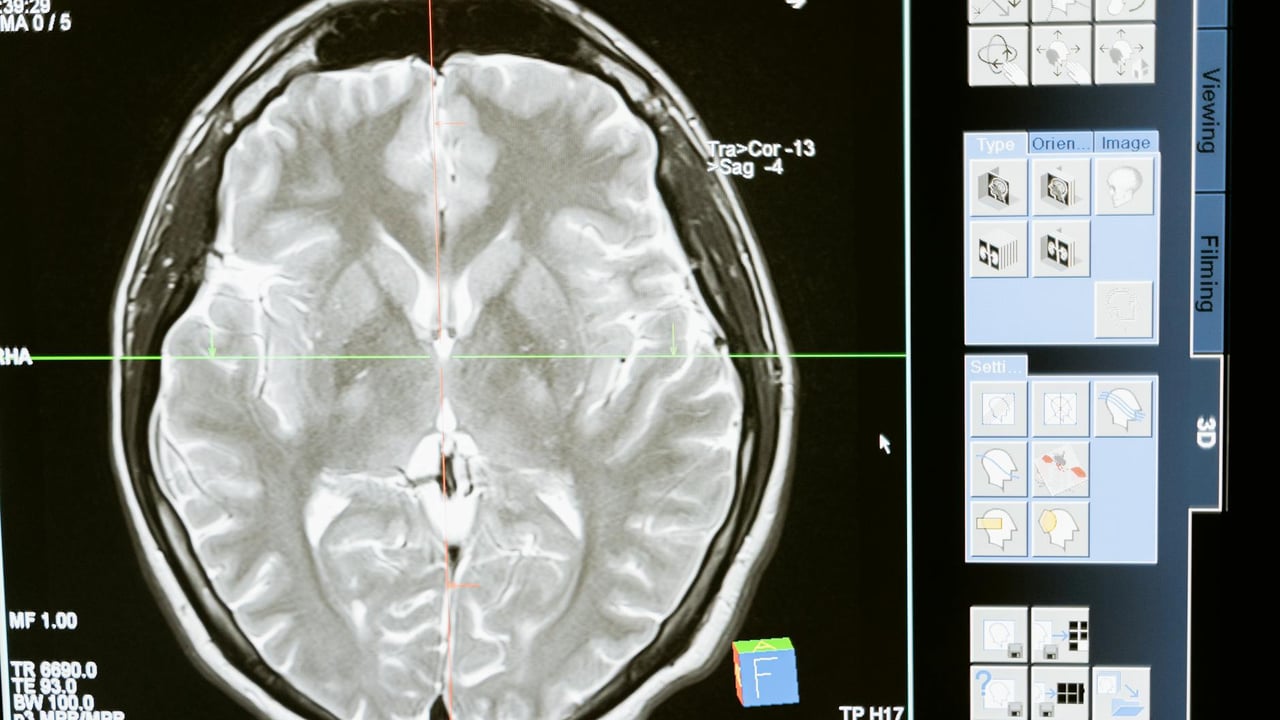

Jieti, founded in 2021, develops minimally invasive implantable BCIs and a supporting stack of electrodes, system hardware, algorithms and surgical robotics. The company says it operates on two business tracks—“brain control” interfaces that restore motor and communication functions, and “neuro‑modulation” therapies aimed at neurological disorders—and has rapidly advanced from lab prototypes to repeated human implants.

Clinical milestones have accelerated. Jieti reported that a second invasive BCI trial completed successfully at the end of 2025: a patient paralysed by a high spinal cord injury was implanted in June 2025 and, after weeks of training, regained stable control of a computer cursor and tablet, and later performed real‑world tasks such as operating a wheelchair and directing a robotic pet with sub‑100 millisecond end‑to‑end response times. A third clinical case concluded in October 2025, and in early 2026 the company implanted what it describes as a domestically first 256‑channel wireless high‑throughput invasive BCI (WRS02), validating brain‑control function in humans.